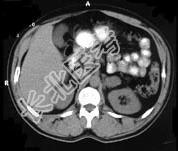

- 多项选择题女,34岁, 无意中发现血压升高4 个月就诊,行CT检查, 如图所示,下列说法正确的是 ( )

A、CT示左侧肾上腺区可见一等密度块影,边界清楚

B、增强扫描,该病灶周边明显强化,中心处强化不明显

C、考虑为左肾上腺腺瘤

D、考虑为左肾上腺嗜铬细胞瘤

E、考虑为左肾上腺转移瘤